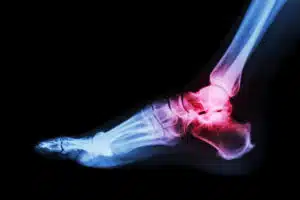

Learn about the symptoms and treatments for dozens of foot and ankle conditions and injuries.